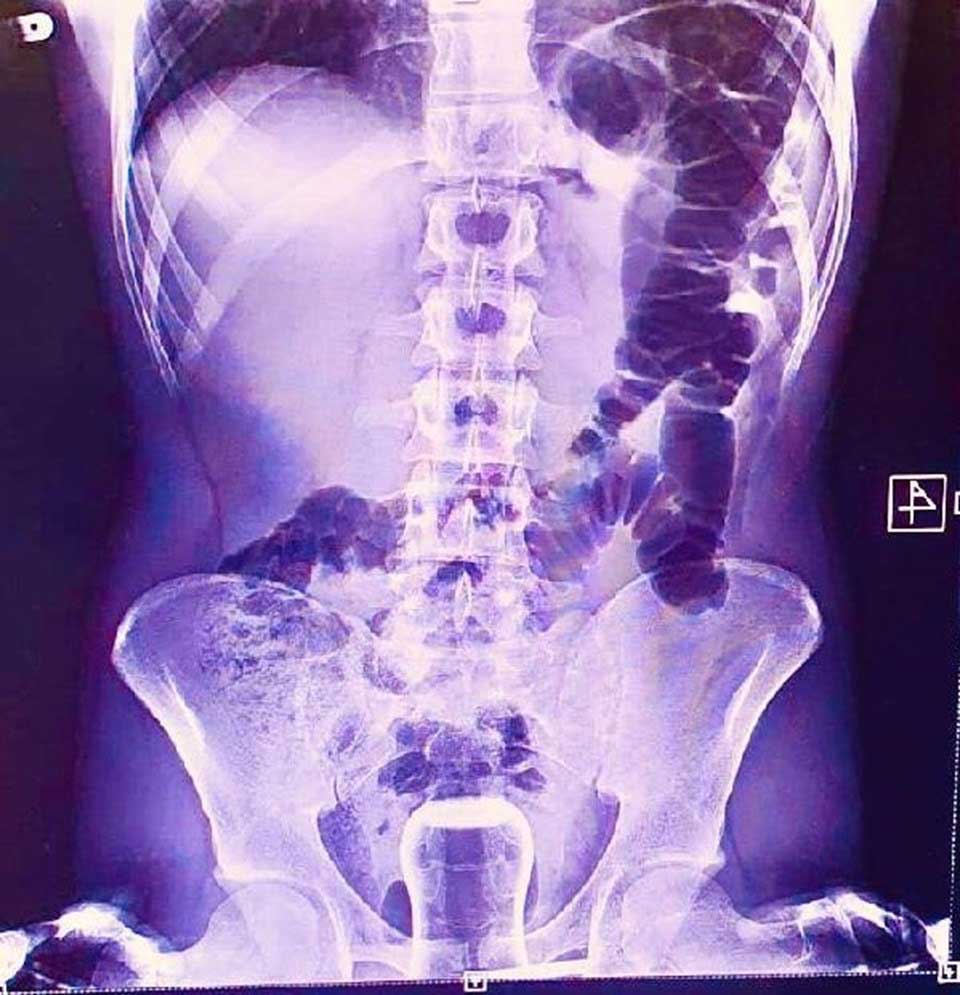

Acil serviste hastanın çekilen röntgeninde anüs bölgesinde çay bardağı görüldü.

Bu kişi genel cerrahi servisinde ameliyata alındı.

Çay bardağı, uzman doktorlar tarafından gerçekleştirilen operasyonla çıkarıldı.

Ameliyatla sancıdan kurtulup eski sağlığına kavuşan hasta doktorlara, uzun zamandır basur hastası olduğunu, hacamatçıya gittiğini ve yağlı çay bardağın kazayla anüs bölgesine kaçtığını ileri sürerek, ameliyattan dolayı teşekkür etti.